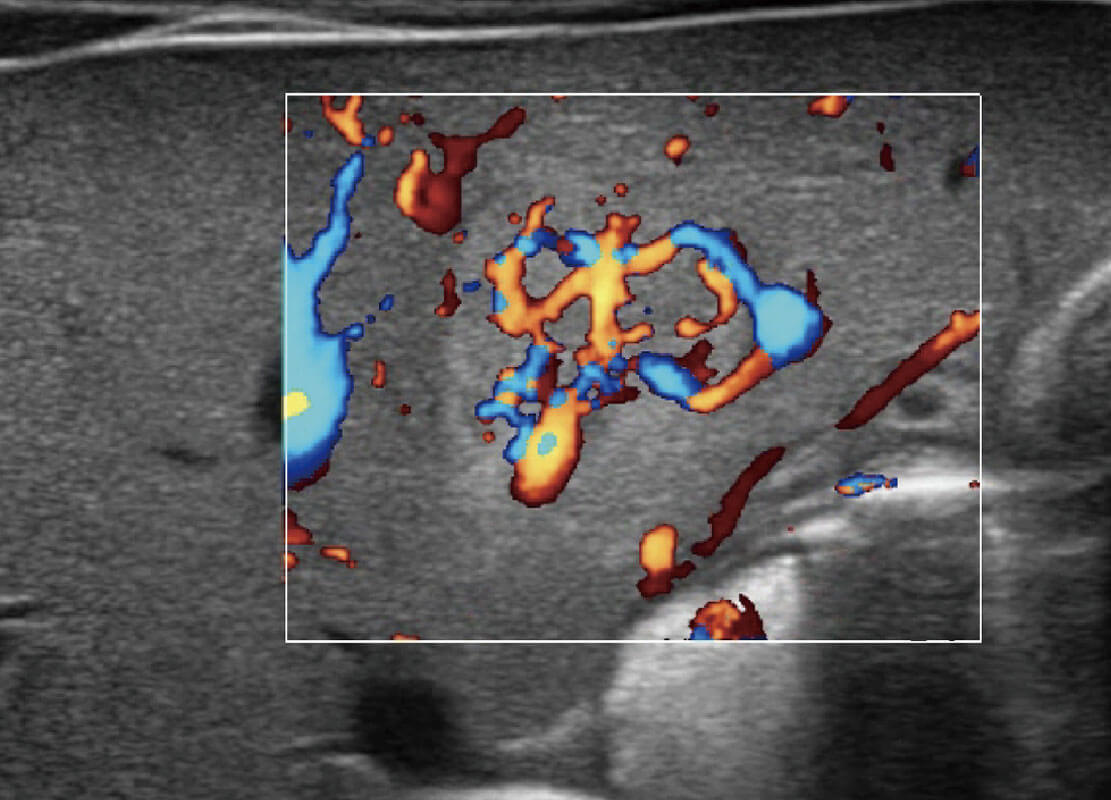

P60搭載寬頻帶線陣探頭、寬景成像、彈性成像技術(shù),為您提供乳腺應(yīng)用方案。P60支持高頻相控陣探頭、線陣探頭、腹部高頻探頭、腹部微凸探頭等,豐富的探頭群搭載敏感的彩色血流成像,適用于新生兒多種臟器檢測(cè)要求,滿足新生兒篩查需求。

新生兒肝血管癌

新生兒脊髓圓錐

新生兒心臟